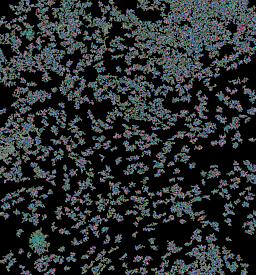

Pancreatic ductal adenocarcinoma is a lethal disease with limited treatment options and poor survival. We studied 83 spatial samples from 31 patients (11 treatment-naïve and 20 treated) using single-cell/nucleus RNA sequencing, bulk-proteogenomics, spatial transcriptomics and cellular imaging. Subpopulations of tumor cells exhibited signatures of proliferation, KRAS signaling, cell stress and epithelial-to-mesenchymal transition. Mapping mutations and copy number events distinguished tumor populations from normal and transitional cells, including acinar-to-ductal metaplasia and pancreatic intraepithelial neoplasia. Pathology-assisted deconvolution of spatial transcriptomic data identified tumor and transitional subpopulations with distinct histological features. We showed coordinated expression of TIGIT in exhausted and regulatory T cells and Nectin in tumor cells. Chemo-resistant samples contain a threefold enrichment of inflammatory cancer-associated fibroblasts that upregulate metallothioneins. Our study reveals a deeper understanding of the intricate substructure of pancreatic ductal adenocarcinoma tumors that could help improve therapy for patients with this disease.